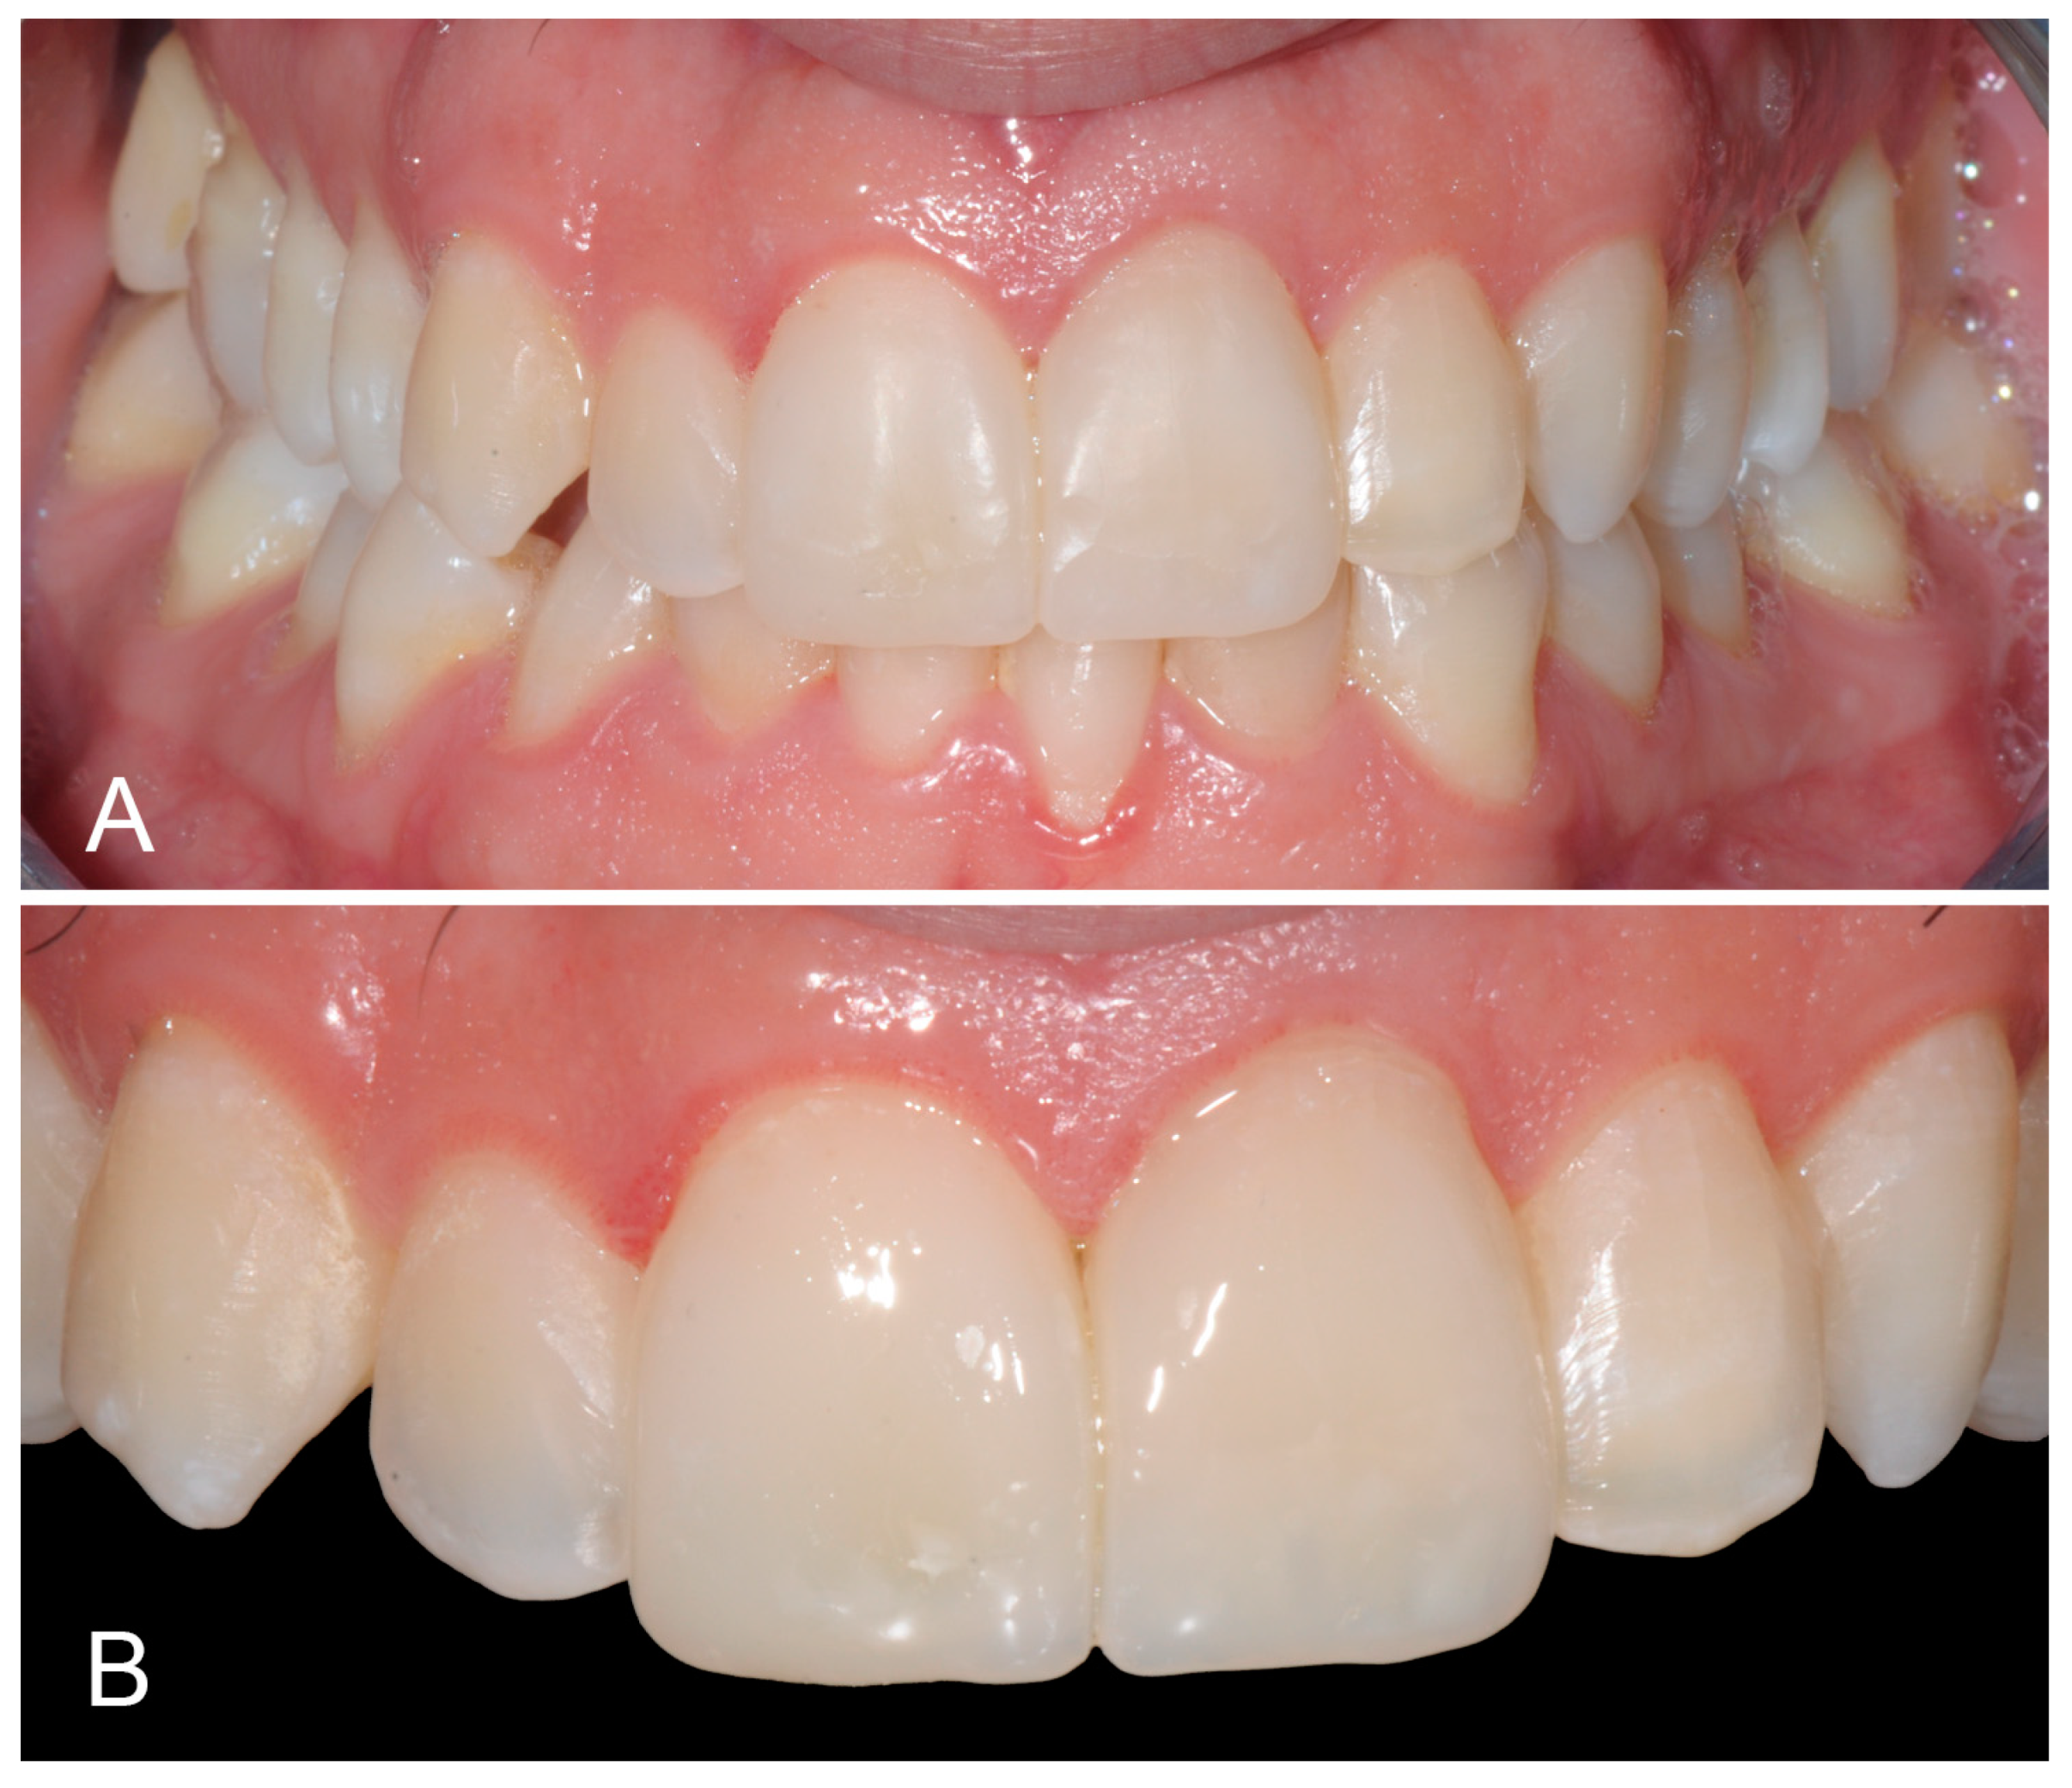

2. Case Report